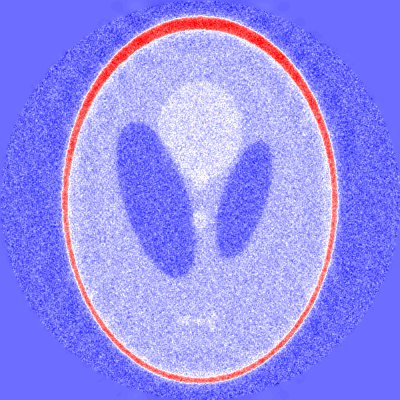

4 Application to X-ray tomography

In this section we apply the concept of filtered DFDs to X-ray tomography as a prime example of an inverse problem in medical image reconstruction. In two spatial dimensions, X-ray tomography can be modeled by the 2D Radon transform. In this section we study filtered DFDs for the Radon transform on L2(2)superscript𝐿2superscript2L^{2}(\mathbb{R}^{2}). Throughout this section, the Fourier transform of a function fL1(n)𝑓superscript𝐿1superscript𝑛f\in L^{1}(\mathbb{R}^{n}) is defined by f(ξ)=nf(x)eiξ,xdx𝑓𝜉subscriptsuperscript𝑛𝑓𝑥superscript𝑒𝑖𝜉𝑥d𝑥\mathcal{F}f(\xi)=\int_{\mathbb{R}^{n}}f(x)e^{-i\langle\xi,x\rangle}\operatorname{d}\!x and extended to functions in L2(n)superscript𝐿2superscript𝑛L^{2}(\mathbb{R}^{n}) by continuity. Its inverse transform is denoted by 1superscript1\mathcal{F}^{-1}. For functions g𝑔g defined on 𝕊1×superscript𝕊1\mathbb{S}^{1}\times\mathbb{R} we write 2gsubscript2𝑔\mathcal{F}_{2}g for the Fourier transform in the second argument.